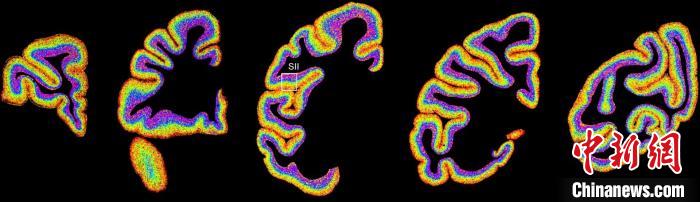

圖為不同類(lèi)型細(xì)胞在獼猴大腦上的分布切片?!≈袊?guó)科學(xué)院腦科學(xué)與智能技術(shù)卓越創(chuàng)新中心 供圖

李澄宇說(shuō),科研人員做的事情好似“查戶(hù)口”,也就是搞明白猴腦里有哪些細(xì)胞、這些細(xì)胞在哪些位置。搞明白這些就形成了一個(gè)大的數(shù)據(jù)集,科研團(tuán)隊(duì)挖掘這個(gè)數(shù)據(jù)集,發(fā)現(xiàn)了很多有意思的現(xiàn)象:比如,興奮性神經(jīng)元、抑制性神經(jīng)元以及非神經(jīng)元在大腦皮層中的分布呈現(xiàn)明顯的特異性,也就是不同細(xì)胞“住”哪,有一定規(guī)律。